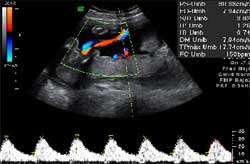

Esta ecografía valora no sólo la medición de nuevo de la traslucencia nucal, sino también la presencia de hueso nasal, la presencia o no de insuficiencia tricúspide, la onda a positiva en el ductos venoso y en algunos casos también se mide el ángulo frontomaxilar.

Debe realizarse por ecografistas expertos y su duración oscila entre los 20-30 minutos. Si existe la presencia de algún marcador de aneuploidía o síndrome de Down, con un riesgo intermedio en el cribado combinado, te aconsejarán realizar una amniocentesis del gemelo con síntomas de anomalías cromosómicas

La amniocentesis es una técnica que consiste en la extracción de líquido amniótico de la bolsa que aloja el bebé durante una gestación. Se realiza introduciendo una aguja muy fina a través de la pared abdominal hasta llegar al interior de la cavidad amniótica donde está el feto rodeado de líquido. Este procedimiento se hace bajo control ecográfico y debe realizarse por ecografistas experimentados. Esta técnica puede emplearse con fines diagnósticos o con fines terapéuticos.

A partir de ahora comienzan las ecografías para descartar la presencia del síndrome de tranfusión fetofetal. En ellas se valora la viabilidad de los fetos, se medirán los tamaños de las vejigas de los hermanos, así como la cantidad de líquido amniótico de cada bolsa. ¿Cómo? Según las columnas máximas de líquido amniótico: si en una bolsa la columna máxima de líquido amniótico es menor de 2 centímetros y en la otra es mayor de 8 centímetros, podemos decir que estamos ante un síndrome de transfusión fetofetal.